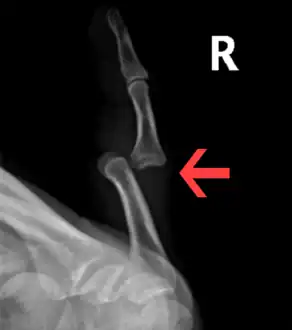

Dislocation of the left index finger

Radiograph of right fifth phalanx bone dislocation- Radiograph of left index finger dislocation